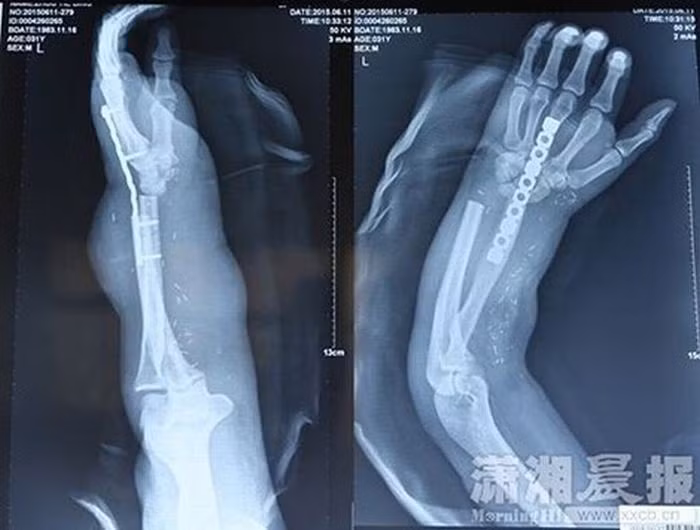

Các bác sỹ Trung Quốc vừa thực hiện một ca phẫu thuật đặc biệt để cứu bàn tay của một bệnh nhân bằng cách gắn nó vào chân của chính bệnh nhân đó trong khi chờ phẫu thuật. Đó là nguồn gốc của cảnh tay mọc từ chân như trong hình.

Zhou đã được đưa tới bệnh viện Xiangya để chữa trị. Tuy nhiên do bàn tay và cả cánh tay của anh đã bị thương nặng, các bác sỹ không thể nối ghép tay lại cho anh ngay nên phải nối bàn tay bị cắt rời vào chân bên phải của anh để các dây thần kinh và gân có thời gian hồi phục.

Bàn tay của anh Zhou đã được cứu sống và dần hồi phục nhờ được gắn vào chân trong suốt 1 tháng.

Sau đó, các bác sỹ đã tiến hành phẫu thuật gắn lại bàn tay vào cánh tay anh Zhou. Ca phẫu thuật kéo dài 10 tiếng đồng hồ.